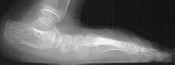

RADIOGRAPHIC EXAM:

Preoperative weight-bearing lateral radiographs of the feet reveal the

following:

Preoperative X-rays:

- Left Talocalcaneal angle is 48 degrees, Talonavicular angle is 56 degrees

- Right Talocalcaneal angle is 44 degrees, Talonavicular angle is 40

degrees